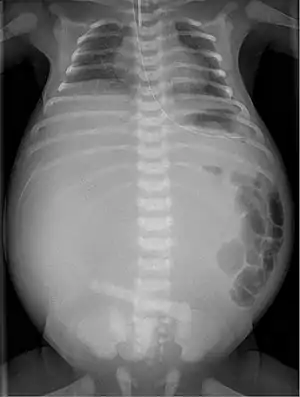

| X-ray of a newborn with meconium pseudocyst resulting from bowel perforation. In this case the cause was atresia of the terminal ileum. There is a fine rim of calcification surrounding the big pseudocyst which shifts the other intestinal structures outwards. | |

Twenty percent of infants born with meconium peritonitis will have vomiting and dilated bowels on x-rays which necessitates surgery.

Meconium peritonitis is sometimes diagnosed on prenatal ultrasound[1] where it appears as calcifications[2] within the peritoneum.